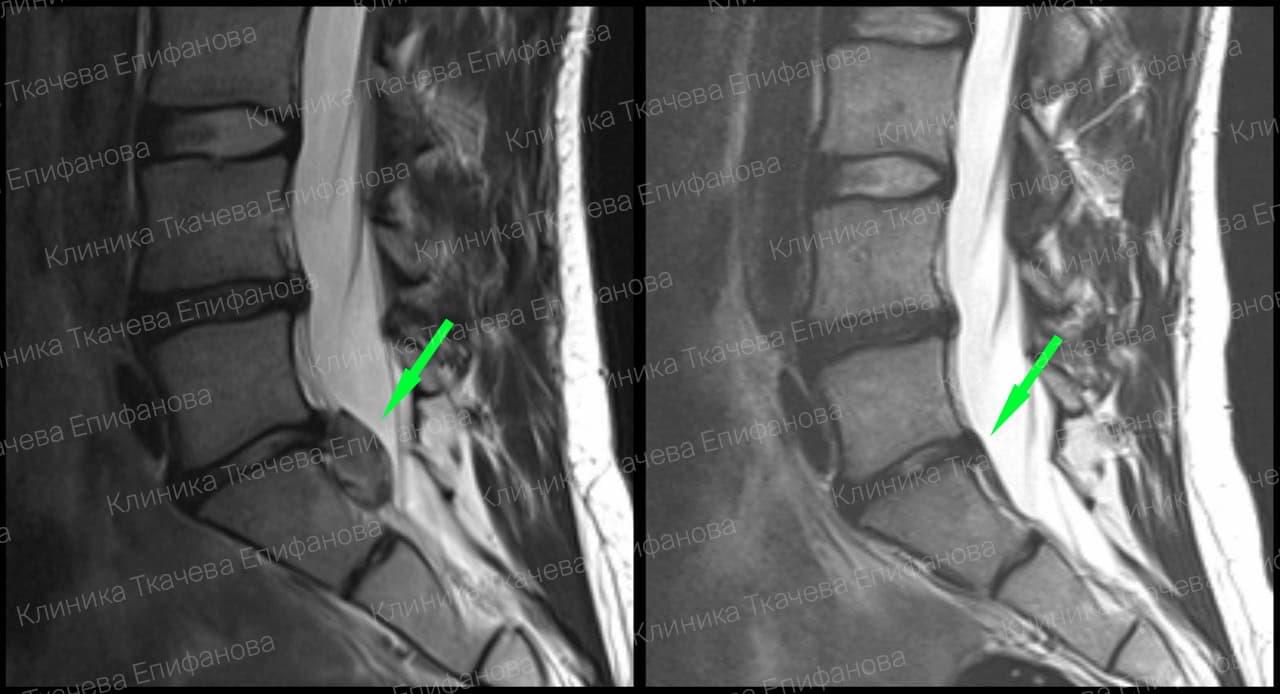

* Резорбция — процесс уменьшения грыжи диска за счет естественных физиологических способностей организма. Это основа эффективного лечения грыжи и альтернатива операции.

Метод модулируемой резорбции позволяет ускорить этот процесс, взять боль под контроль и улучшить качество жизни.